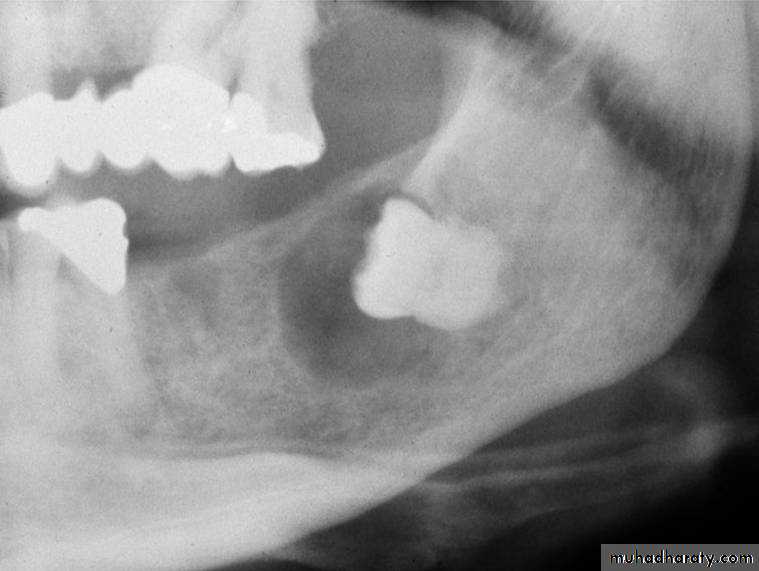

Cysts (abnormal, closed-walled sac present in or around tissue): usually X-ray detected and removed before they enlarge and destroy bone tissue. Some types are:A- Dentigerous: cystic sac containing a tooth or tooth bud particle.

B- Radicular: cyst located alongside or at the apex of a Tooth root; also called periapical cyst.C- Ranula: cystic tumor found on the underside of the tongue or in the sublingual or submaxillary ducts; usually the result of a blocked duct.